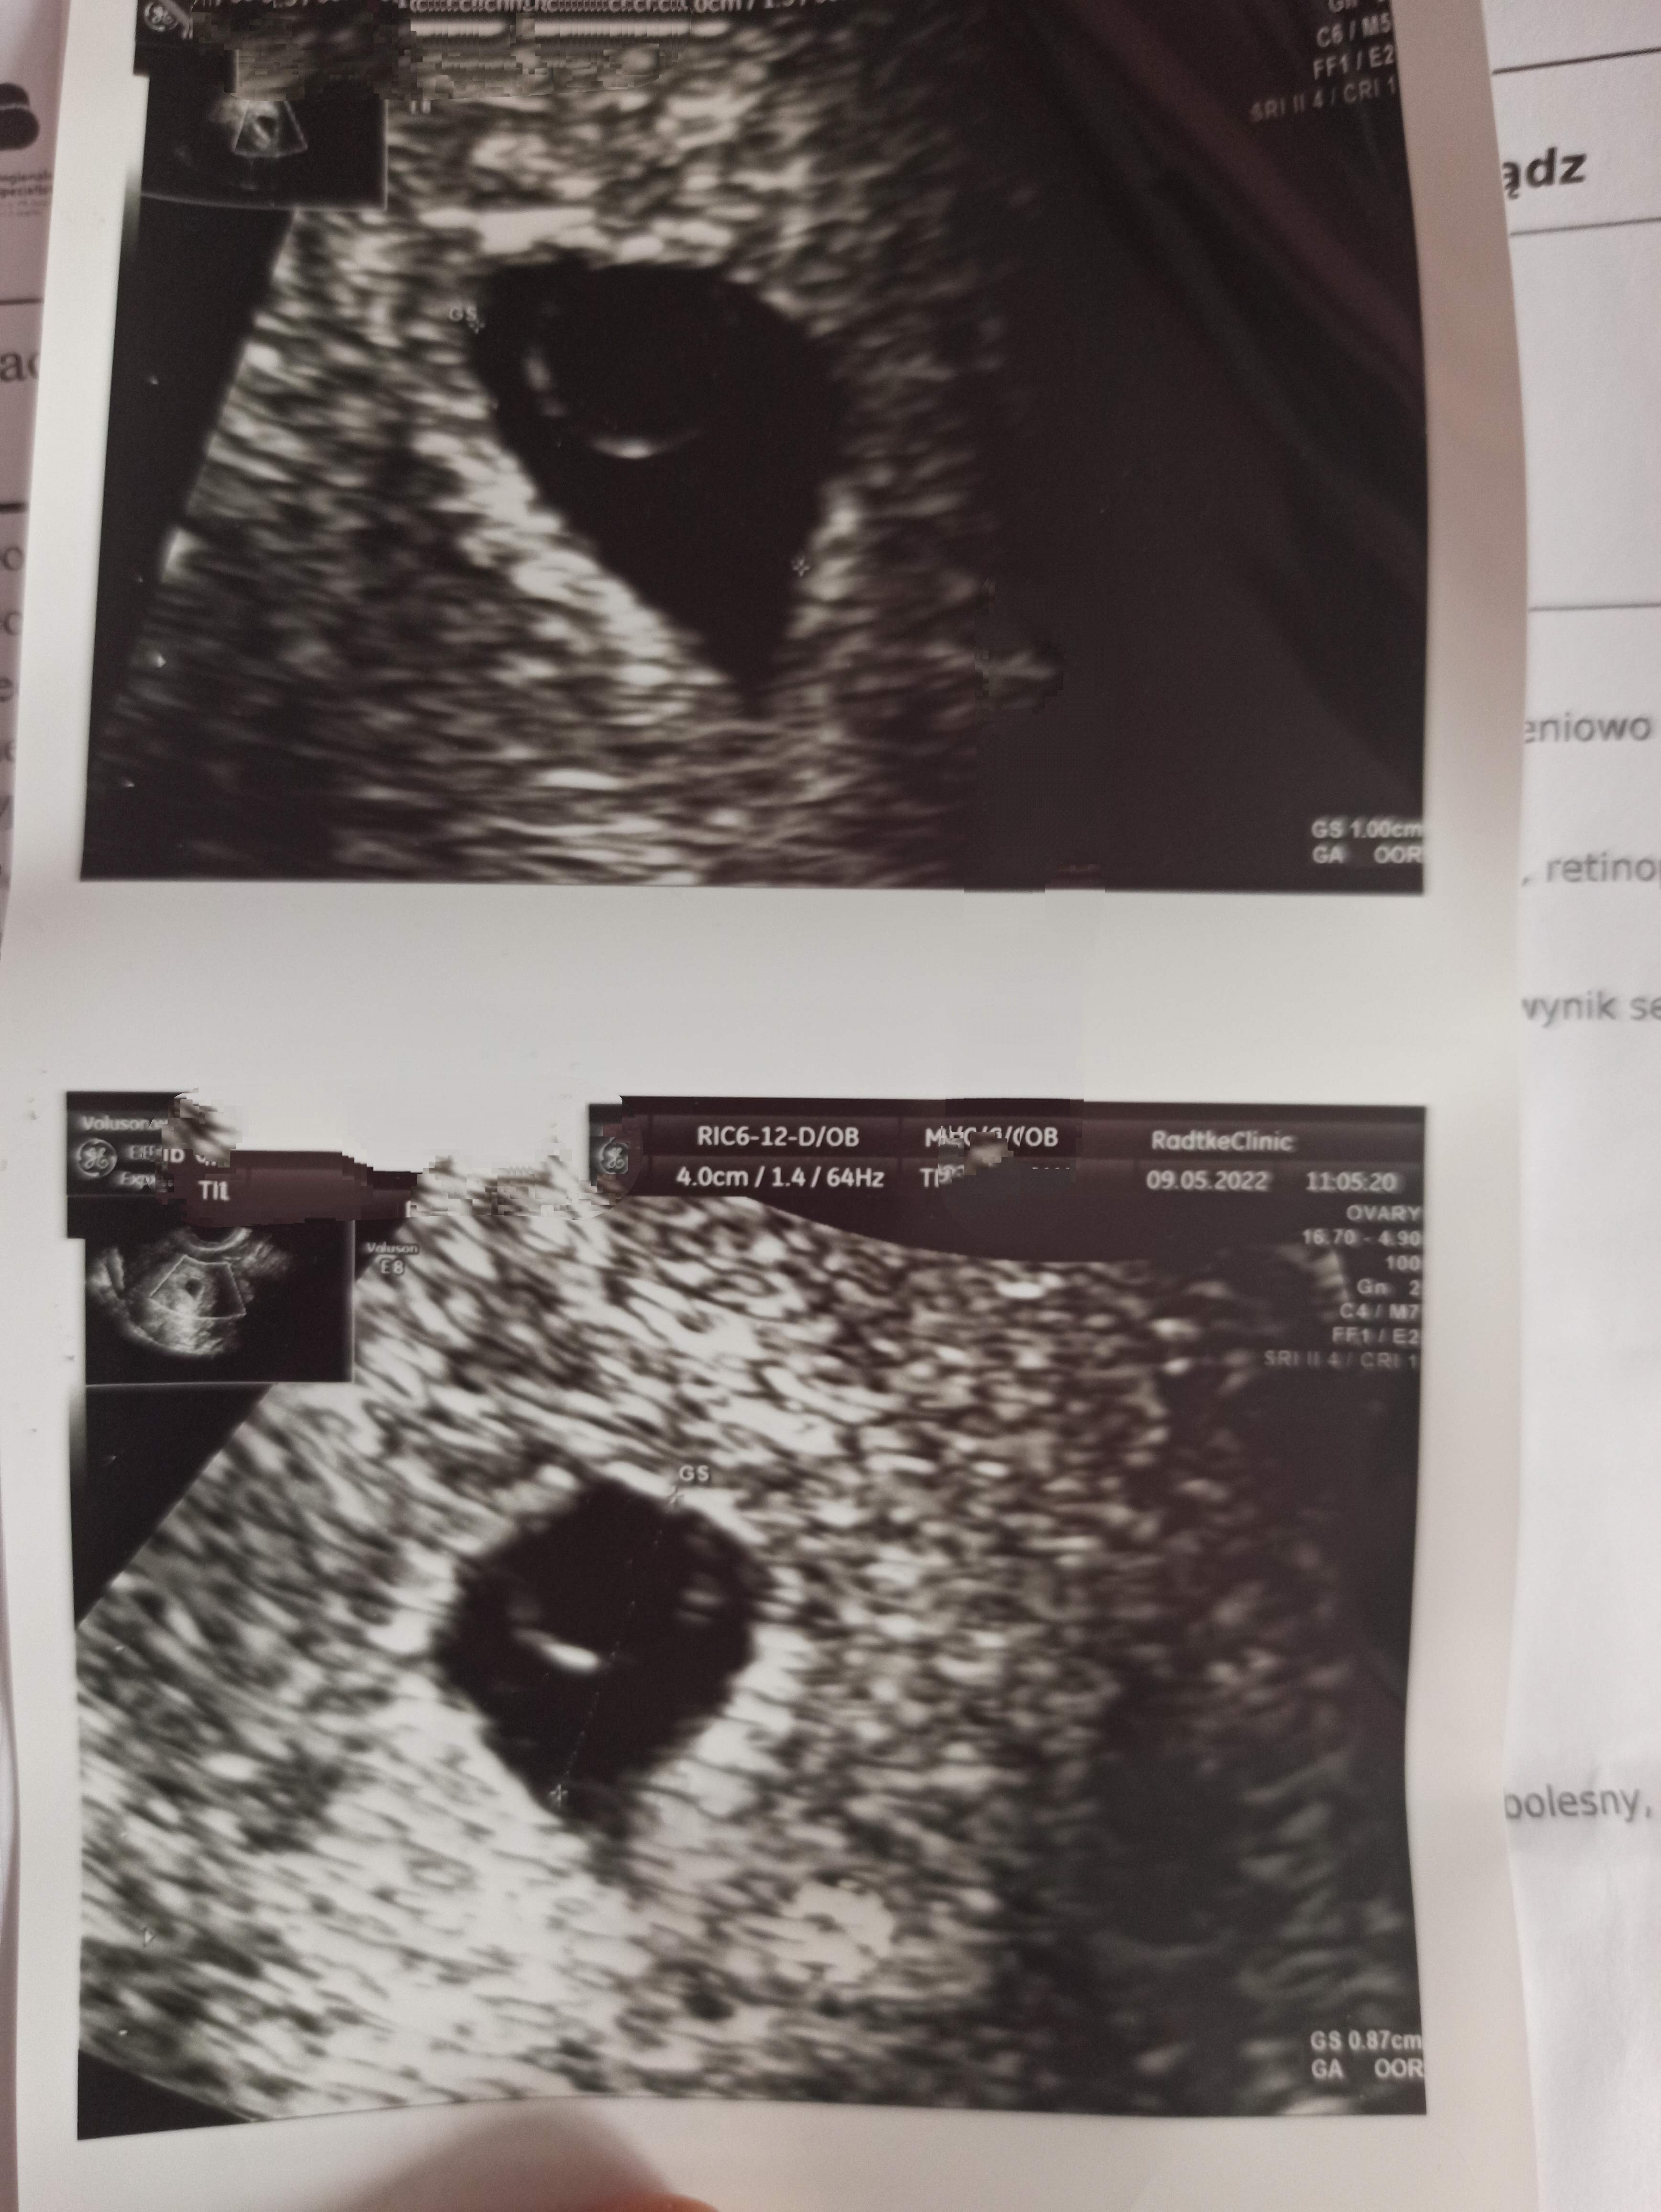

Hej byłam na USG dokładnie w 6+2 a tam na obrazie widać jedynie pęcherzyk ciążowy 10mm i pęcherzyk żółtkowy który zajmuje prawie połowę ciążowego. Dodam, że nie ma u mnie możliwości aby przesunęła się jakoś bardzo owulacja, musiała być 13-14 dnia cyklu, bo 23 dnia miałam już cień cienia na teście z moczu, a 25 dnia beta z krwi potwierdziła (19,4).